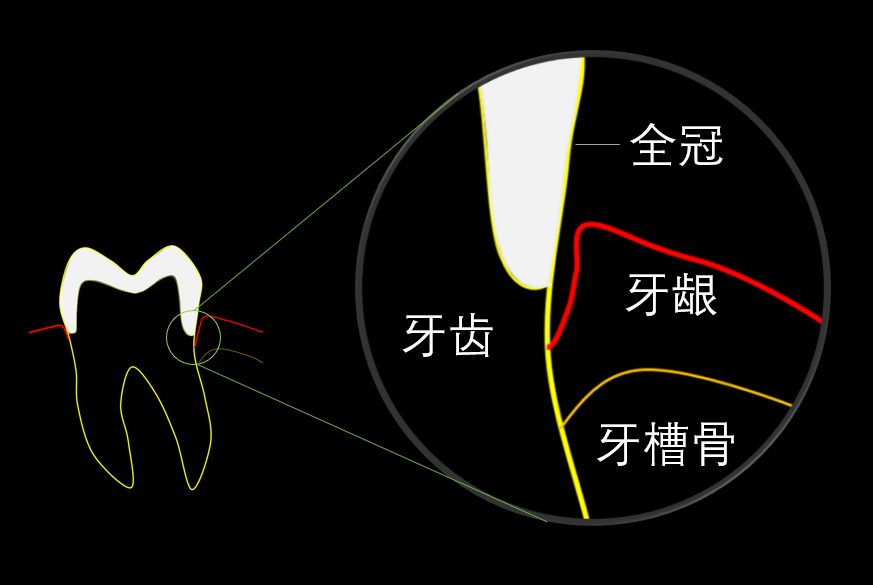

全冠是一种较常见的修复方式,主要用于修复牙齿缺损过大的情况。对于根管治疗后的牙齿,医生通常会建议做全冠。在做全冠时,大部分人会问医生一个问题:我的牙冠能用多久?毕竟牙冠修复也是一笔不小的费用。

图1. 上前牙的全瓷冠修复

图2.全冠边缘示意。 全冠并不会将牙齿暴露在口腔内的部分全部罩住,否则会引起牙龈的炎症及牙槽骨的吸收。牙龈和牙根之间有一段不是连在一起的,叫龈沟,和指甲沟有点像。为了美观或者戴得稳,全冠的边缘经常会放在这里。这就要求全冠的边缘要尽量密合,否则在这个位置容易堆积菌斑,导致继发龋或者牙周炎。

图2.全冠边缘示意。 全冠并不会将牙齿暴露在口腔内的部分全部罩住,否则会引起牙龈的炎症及牙槽骨的吸收。牙龈和牙根之间有一段不是连在一起的,叫龈沟,和指甲沟有点像。为了美观或者戴得稳,全冠的边缘经常会放在这里。这就要求全冠的边缘要尽量密合,否则在这个位置容易堆积菌斑,导致继发龋或者牙周炎。